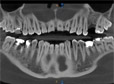

Jedyny taki trójwymiarowy tomograf w Słubicach i woj. lubuskim. Sprawdź ofertę Exclusive Dental Studio

- Kategoria: Aktualności

Potrzebujesz tomografii zatok, ucha, szczęki, uzębienia? Zajrzyj do kliniki stomatologicznej Exclusive Dental Studio. Dzięki trójwymiarowemu tomografowi CARESTREAM CS 9600 – jedynemu w Słubicach i całym woj. lubuskim, badanie nigdy nie było tak dokładne, bezpieczne i szybkie.

Potrzebujesz tomografii zatok, ucha, szczęki, uzębienia? Zajrzyj do kliniki stomatologicznej Exclusive Dental Studio. Dzięki trójwymiarowemu tomografowi CARESTREAM CS 9600 – jedynemu w Słubicach i całym woj. lubuskim, badanie nigdy nie było tak dokładne, bezpieczne i szybkie.